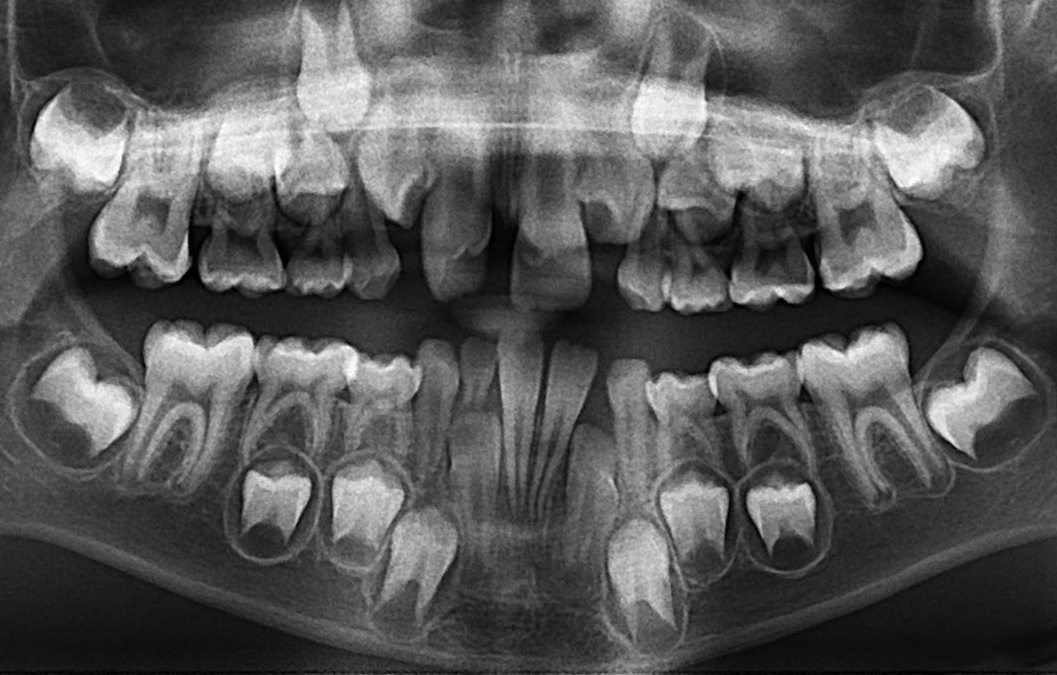

Je constate que l’incisive latérale supérieure gauche (flèche) fait éruption au palais en articulé croisé avec la canine primaire inférieure. Sur la photo de gauche, je constate que les dents supérieures postérieures sont à l’extérieure des dents postérieures inférieures. Il n’y a pas d’articulé croisé postérieur.

Je crois qu’il est indiqué de procéder à l’extraction des 4 canines primaires (marquée d’un X) afin de faciliter l’alignement des dents antérieures et éviter l’articulé croisé 22/73.

Une expansion est possiblement indiquée. Si tel est le cas, je recommande un disjoncteur fixe. Un appareil d’expansion amovible ne produit pas une expansion de l’os basal et favorise une bascule des dents postérieures.

Toutefois, étant donné que votre fils a déjà subi de l’expansion et que l’extraction des canines primaires permettrait un meilleur alignement des incisives, je procéderais aux extractions des dents primaires et révaluerais dans 6 mois. Il sera toujours temps de faire de l’expansion.